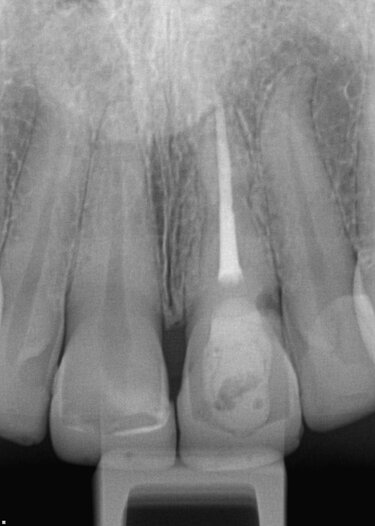

• Root canal therapy #2-1 with lingual composite filling (Figs. 7, above and 8, below)

Fig. 8. Initial examination and x-rays revealed the root canal therapy with lingual composite filling.